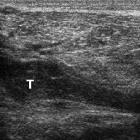

Post-thrombotic

aneurysmal dilatation of the hypogastric vein. 5 years earlier, longitudinal (a) and transverse (b,c) ultrasound images showed chronic deep venous thrombosis (T) of the right lower limb, from the popliteal to the common femoral vein.